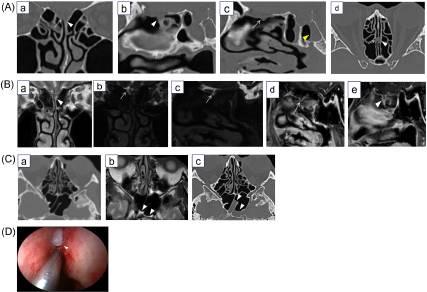

进行头部CT和磁共振成像(MRI)以确定脑脊液漏的位置。CT显示双侧筛板不清,双侧嗅裂区筛板可见软组织突出,以左侧为主。左侧蝶窦内有空气液位;因此,怀疑左侧脑脊液漏。MRI显示左嗅裂冠状T2加权图像(T2WI)呈高信号,怀疑有液体成分。三维(3D)MR脑池造影显示右嗅裂信号强度高,与蛛网膜下腔连续,左嗅裂液体信号不清。钆增强T1加权图像(Gd-T1WI)显示,两侧嗅裂的脑膜从筛板突出。CT后约3小时进行MRI检查,在这段短时间内,左侧蝶窦中的液体量增加,这一发现被认为反映了持续的渗漏(图1A)。

进行了内窥镜脑脊液漏修复,结果显示左嗅裂有1-2mm的脑膜膨出,左筛板有脑脊液漏。术后左鼻分泌物症状消失。

图1A CT成像(a)垂直于颅底的冠状位。(b) 矢状位与左嗅裂对齐。(c) 矢状位与右嗅裂对齐。(d) 与颅底平行的轴位。双侧筛板模糊不清,但尚不清楚是否存在骨缺损(a-c)。两个嗅裂中筛板突出的软组织密度以左侧为主,这可能表明泄漏的位置(a-d)。根据患者的症状和左侧蝶窦的液平(c)(黄色箭头),怀疑左侧脑脊液漏。

B 磁共振成像(a) 冠状T2WI。(b) 冠状位3D-MR脑池造影。(c) 3D-MR脑池造影矢状位与右嗅裂对齐。(d) 3D-MR脑池造影矢状位与右嗅裂对齐。(e) Gd-T1WI矢状位与左嗅裂对齐。冠状位T2WI显示左嗅裂有高信号强度,与CT(a)上看到的软组织密度相对应(箭头)。在3D-MR脑池造影中,左嗅裂的信号不清楚,从蛛网膜下腔到右嗅裂(b和c)有连续的高信号强度(箭头)。Gd-TIWI显示双侧(d和e)从筛板突出的脑膜膨出样结构(箭头和箭头)。

1C (a) 轴位CT图像。(b) 在获得CT图像3小时后进行轴向T2WI MRI。(c) 获得MRI图像4天后的轴位CT图像。(d) 在CT和MRI成像之间,左侧蝶窦中的液平增多,表明左侧筛板(a-c)中的脑脊液持续泄漏(b和c中的箭头表示积聚的液体)。右窦内未观察到液平。1D。内镜手术期间,在左嗅裂中发现了一个1-2mm大小的脑膜膨出(箭头)。